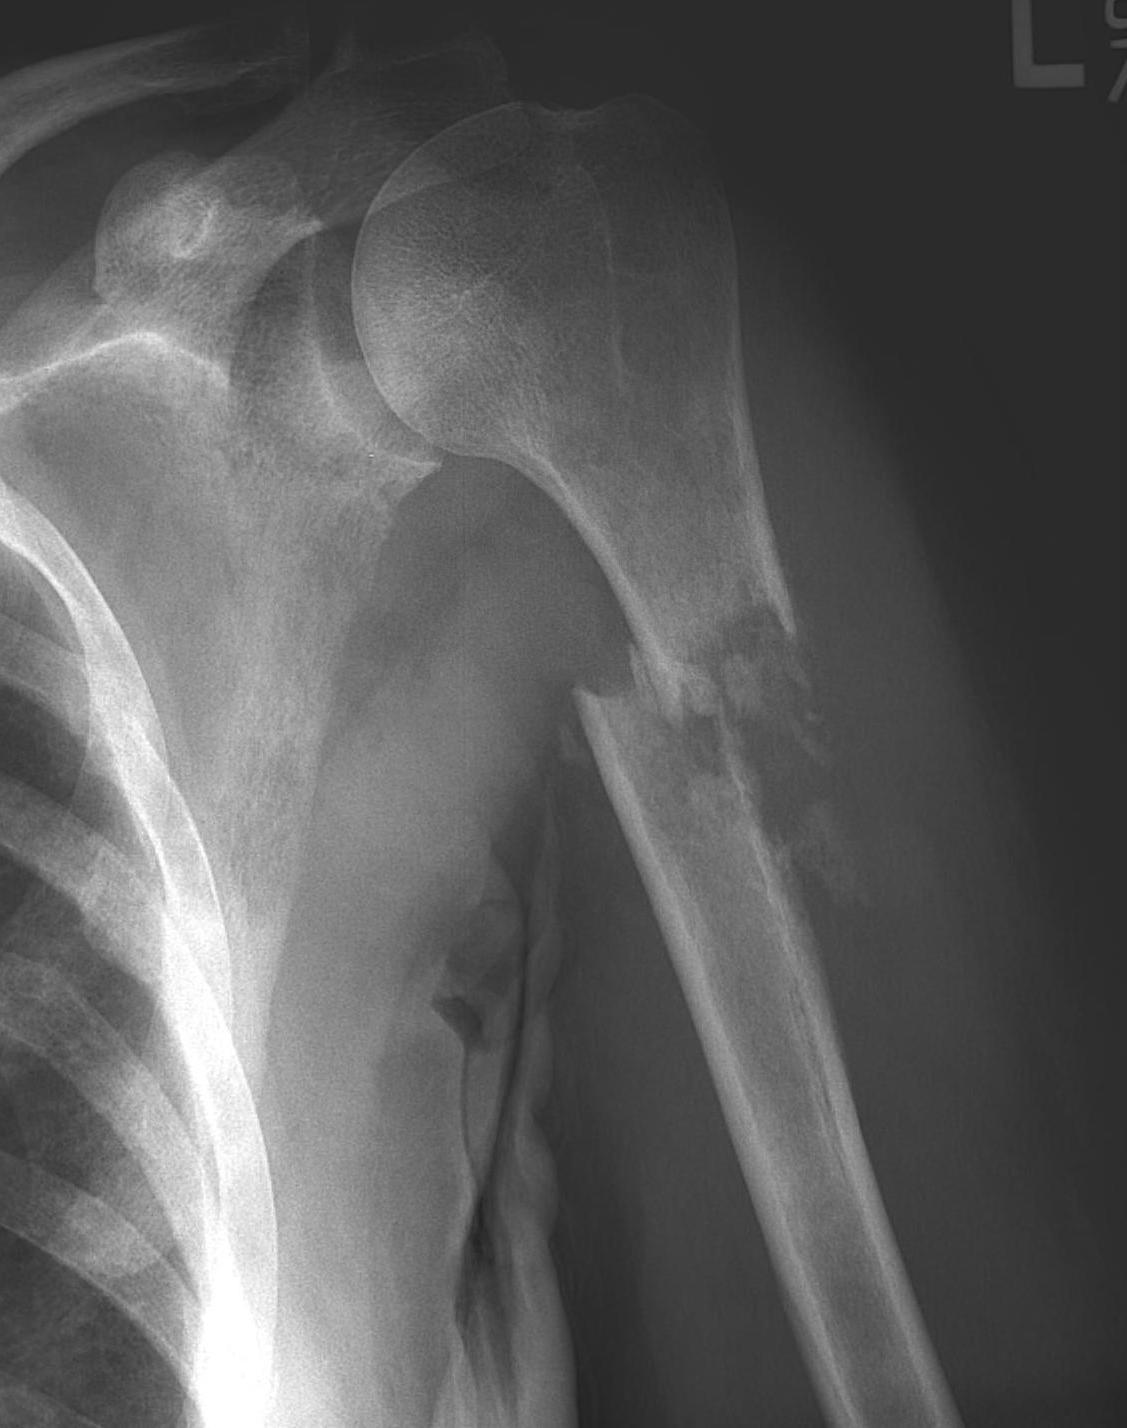

Proximal Humerus

Options

ORIF with plate +/- cement

IMN +/- cement

Tumour prosthesis

Results

Wu et al J Orthop Traumatol 2023

- 45 patients with proximal humerus metastasis

- IM nailing + cement versus plate

- lower blood loss and shorted hospital stay with IMN

- better pain relief with IMN